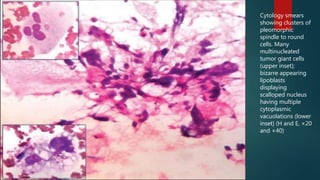

Cytology smears

showing clusters of

pleomorphic

spindle to round

cells. Many

multinucleated

tumor giant cells

(upper inset);

bizarre appearing

lipoblasts

displaying

scalloped nucleus

having multiple

cytoplasmic

vacuolations (lower

inset) (H and E, ×20

and ×40)

Cytology smears showing clustersof pleomorphic spindle to round cells. Many multinucleated tumor giant cells (upper inset); bizarre appearing lipoblasts displaying scalloped nucleus having multiple cytoplasmic vacuolations (lower inset) (H and E, ×20 and ×40)